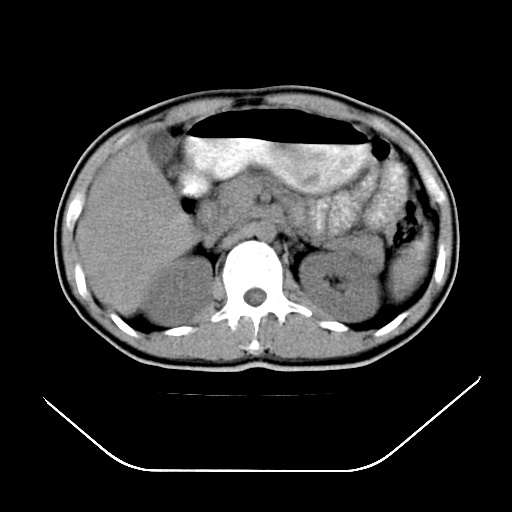

以下是引用深泽交通医院在2008-7-17 12:05:00的发言:[br]肝门淋巴结肿大;胆结石

以下是引用随光逐影在2008-7-17 17:52:00的发言:[br]1)胆囊结石。2)肝门及胰头区淋巴结肿大可能(原因不明);建议行进一步检查。

以下是引用卜一在2008-7-17 16:37:00的发言:[br]支持胆囊结石!!!至于胰头区病变——建议强化后再定论!